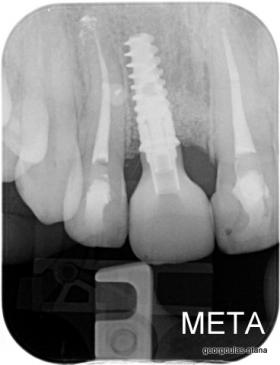

Η κοπέλα αυτή ήρθε στο ιατρείο με κάταγμα στον δεξιό άνω κεντρικό τομέα. Το δόντι είχε απονευρωθεί στο παρελθόν και είχε αποκατασταθεί με βιδωτό άξονα κ ανασύσταση με ρητίνη και το αισθητικό αποτέλεσμα ήταν φτωχό. Η ασθενής ήθελε να είναι καλυμμένη αισθητικά για όσο χρονικό διάστημα θα διαρκούσε η θεραπεία. Πραγματοποιήθηκε τομογραφία κωνικής δέσμης (CBCT) στην περιοχή και αποφασίστηκε να γίνει εξαγωγή του δοντιού, διατήρηση του όγκου του φατνίου και 3 μήνες μετά τοποθέτηση εμφυτεύματος με ταυτόχρονη χρήση μοσχευμάτων σκληρών κ μαλακών ιστών  για βέλτιστο αισθητικό αποτέλεσμα. Το εμφύτευμα αποκαταστάθηκε με υβριδικό κολόβωμα από διπυριτικό λίθιο και ολοκεραμική στεφάνη από διπυριτικό λίθιο (Emax). Καθ’ όλη τη διάρκεια της θεραπείας, η ασθενής ήταν καλυμμένη αισθητικά με γέφυρα Meryland  συγκολλημένη στα δύο διπλανά δόντια. Μετά την οστεοενσώματωση του εμφυτεύματος και πριν την τελική αποκατάσταση, τοποθετήθηκε στο εμφύτευμα προσωρινή εργασία με σκοπό τη βελτίωση των ούλων.